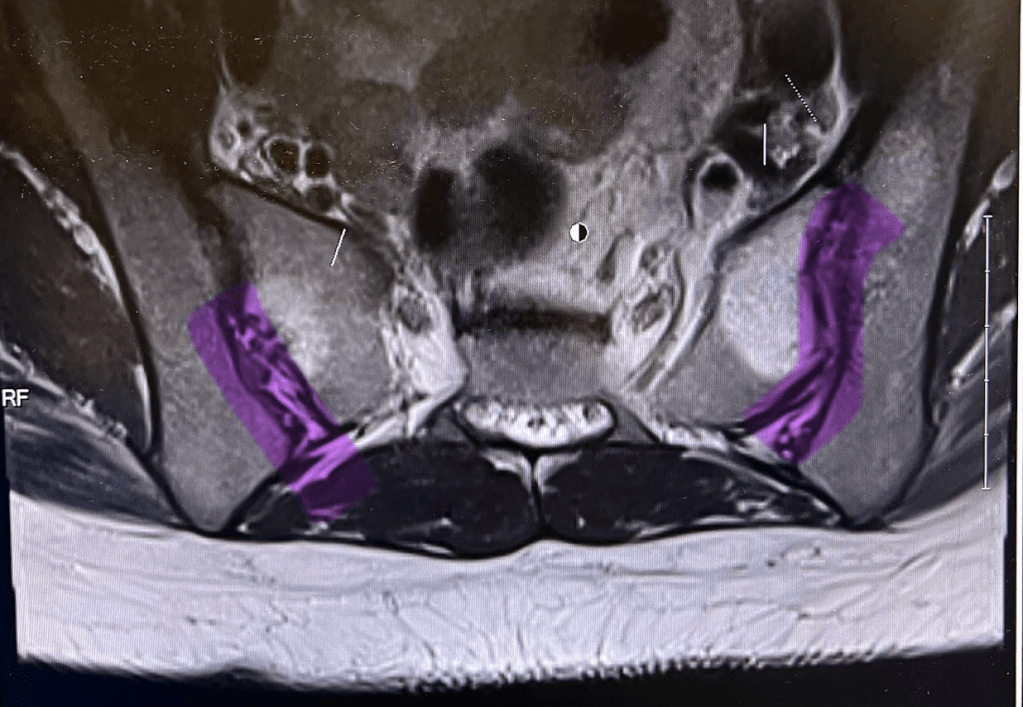

She starts throwing medical jargon at me while we’re looking at the images.

Then we get to the mother of all MRI images. My first question: “Oh, are those my butt cheeks? They look really good!”

Dr. Rickert, the kindest doctor I think I’ll ever come across, chuckles and says, “I can see why you think that, but that’s actually your back muscles and they do look really good!”

Then she hits me with, “but do you see that white stuff here and here? The 2/3 full on the left side and the 1/3 full on the right side? That’s not good.”

And she tried to tell me what all of the white stuff meant but by now, I can’t even think straight. I take a picture of the MRI image on the screen.

Dr. Rickert looks at me and says, “Because of this image, I agree with transferring your care from Spine Unit to Rheumatology. If it doesn’t work out with them, come back and I can try a couple of things here.”

The office didn’t have a way to view my MRI images, but Mom had the picture I sent her of the infamous MRI image from the appointment with Dr. Rickert ready to show Dr. Goodman.

He took a good look at the picture and then said, “Some people come with back pain and nothing to show for it. You’ve come with back pain and A LOT to show for it. There’s a lot of bone marrow edema in your SI joints, Kate.”

Bone marrow edema (BME) is a condition characterized by an accumulation of fluid in the bone marrow. (AKA "the white stuff"!)

Then he continued, “and there’s significant erosion here and the beginning of erosion here”, pointing to my right SI joint and then my left SI joint.

SI joint erosion refers to the loss of bone tissue in the sacroiliac joints (where the bottom of your spine connects to your pelvis).

Bowtie-white-coat-wearing-doctor say what?

None of the other doctors who have looked at my MRI images have said anything about erosion! Turns out the purple is the erosion he’s referring to:

So after all that, Dr. Shung was right.

I do have Ankylosing Spondylitis. Gosh, what the absolute f**k.

The good news: Dr. Goodman believes we can reverse the bone marrow edema!

The bad news: We cannot reverse the erosion of my right SI joint or stop the erosion that has already started in my left SI joint.

It turns out the yelp I let out with Dr. Rickert is most likely from the SI joint erosion on the right side. I have less bone marrow edema on right side, but a far more significant amount of joint erosion than the left side.